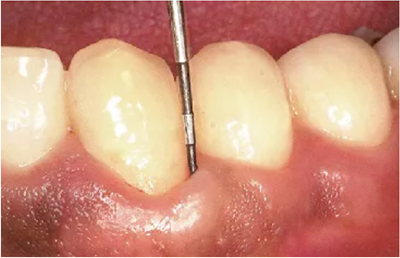

● 鄰接面正下方的探診

鄰接面的正面檢測(cè)方法。注意大約是在鄰接面部分的中央位置處,將探針略傾斜插入鄰接面的中央點(diǎn)。

檢測(cè)鄰接面正中點(diǎn)下方的牙周袋,探針是無法與牙軸平行插入的。但是緊靠著鄰接點(diǎn)平行于牙軸插入探針,可以檢測(cè)到難以檢測(cè)的鄰接面牙周袋深。

如果從斜側(cè)插入探針檢測(cè)沒有一定的標(biāo)準(zhǔn),那么每次測(cè)出的數(shù)值都會(huì)各不相同,得到的數(shù)據(jù)難以正確分析出問題所在。